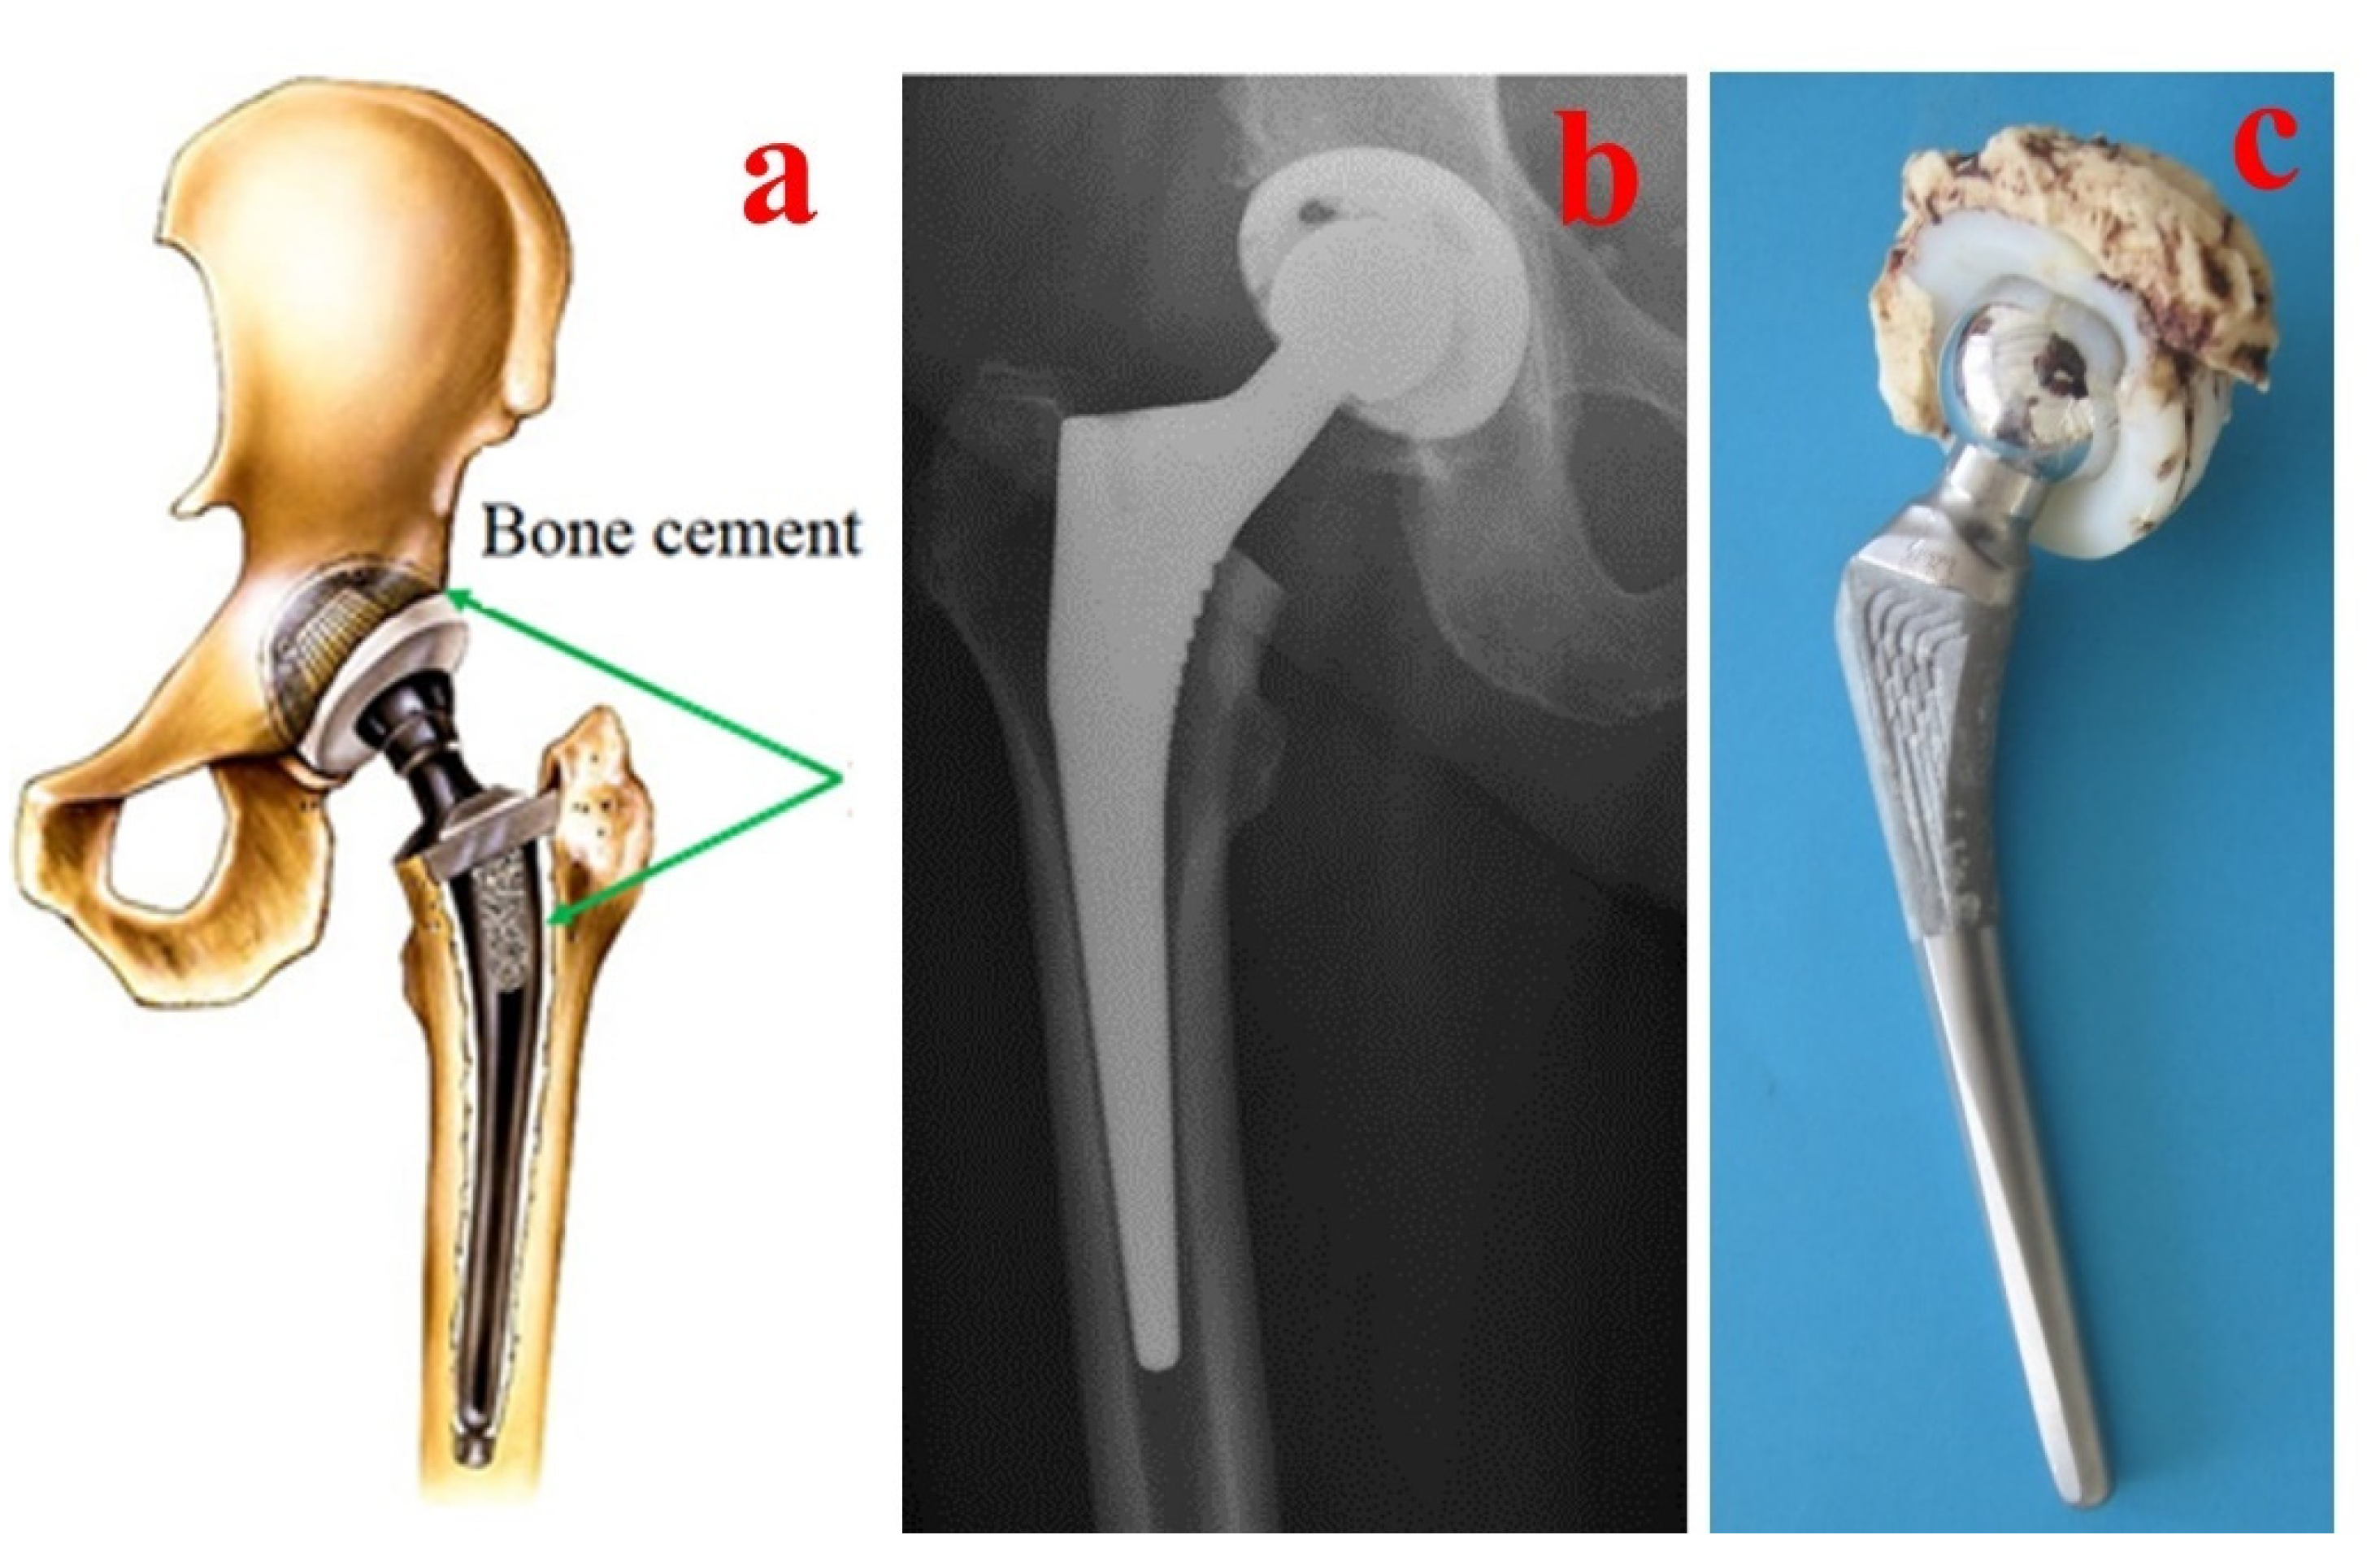

Materials Free FullText Bone Cements Used for Hip Prosthesis How Does Bone Cement Work    polymethyl methacrylate is commonly known as bone cement and is widely used for implant fixation in various.   bone cement, or polymethylmethacrylate (pmma) cement, is widely used to fix joint replacement.   bone cement is a crucial component in orthopedic surgeries, serving as a binding agent to anchor prosthetic devices, such as joint.   bone cement has proven particularly. How Does Bone Cement Work.

Materials Free FullText Bone Cements Used for Hip Prosthesis How Does Bone Cement Work    bone cement, or polymethylmethacrylate (pmma) cement, is widely used to fix joint replacement.   polymethyl methacrylate is commonly known as bone cement and is widely used for implant fixation in various.   there are many factors that influence the properties and behavior of bone cement.   bone cement is a crucial component in orthopedic surgeries, serving as a binding. How Does Bone Cement Work.